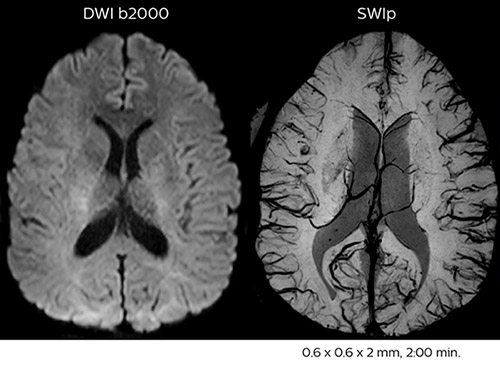

Using MultiBand SENSE allowed the staff to improve their diffusion quality. “Our diffusion sequence was already fast before, about 40 seconds. Now with Elition, it still lasts 40 seconds, but we improved the spatial resolution by 0.2 mm and use high b-values to be more sensitive to visualize changes related to acute stroke,” says Dr. Savatovsky. “We now also developed a high resolution DTI sequence (1.3 x 1.3 x 2 mm) that can be reformatted and takes 2 to 5 minutes depending on the coverage. We use it every time we have a doubt, or when we expect the diffusion to be abnormal but don’t see that on the fast sequence. We occasionally spot small ischemic infarctions that would not have been visible with the regular diffusion sequence.”

In this patient with acute right motor deficit and aphasia, the b2000 diffusion weighted image is normal. The SWIp image demonstrates more prominent veins in the right hemisphere, which could reflect increased deoxyhemoglobin contents. Fast ASL shows low CBF regions in the left frontal lobe. A follow-up ASL after one hour demonstrates high CBF values in the same area. The final diagnosis was migraine with aura.